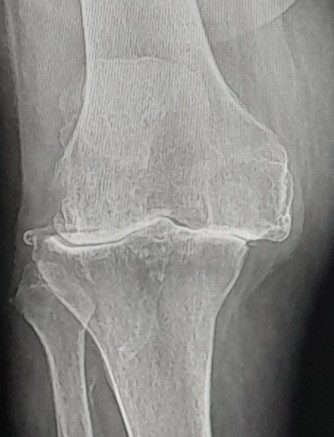

Radiograficamente i segni caratteristici sono:

- Riduzione dello spazio articolare che può colpire uno o entrambi i compartimenti(artrosi monocompartimentale mediale o laterale) causato dalla degenerazione cartilaginea.

- Speroni ossei definiti Osteofiti.

- Cavità di osso degenerato dette geodi.